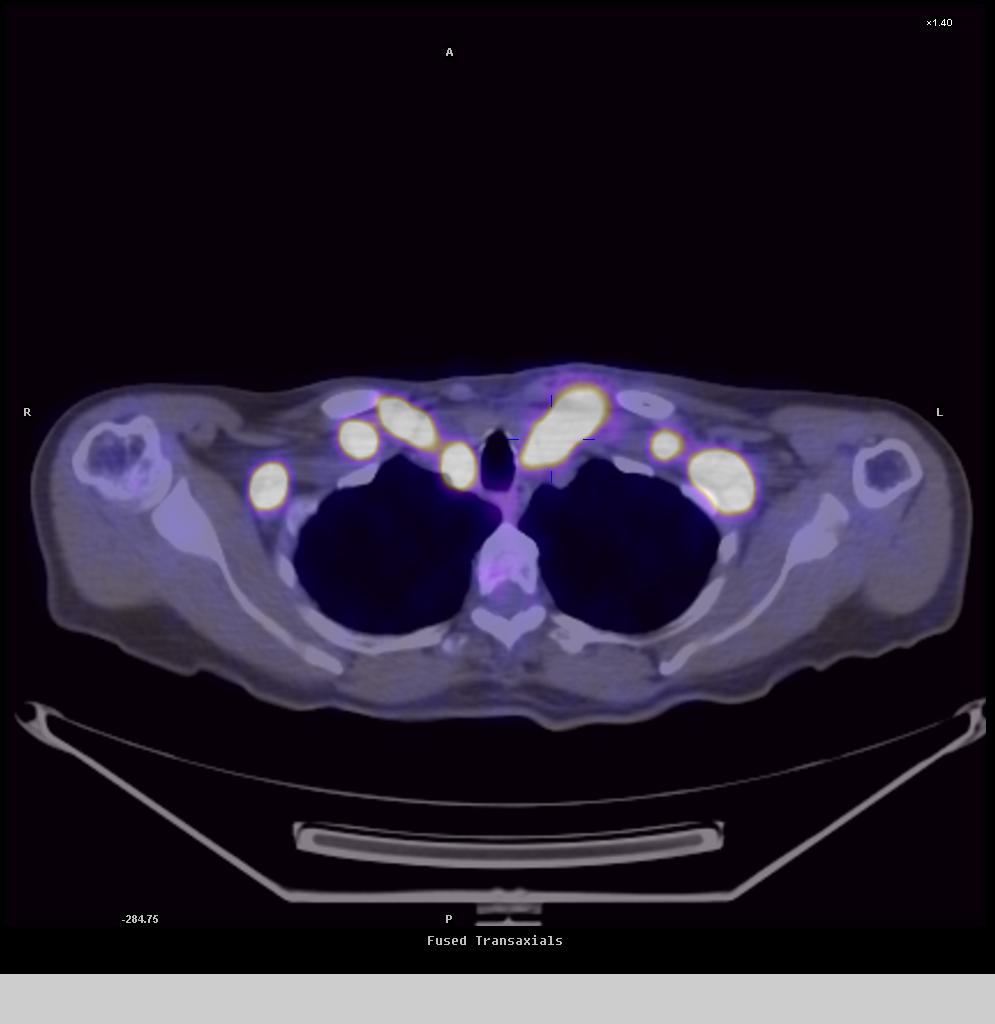

Below, you’ll find scan images showcasing the capabilities of our advanced imaging technology in detecting these conditions.

See the difference our technology can make.